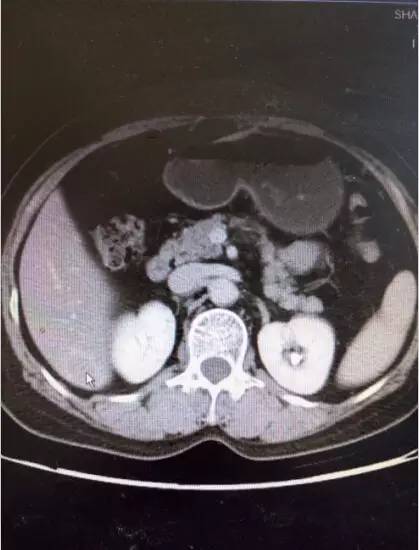

上腹部增强CT:1.肝右叶S6段占位,肿瘤性病变不除外2.肝脏小血管可能3.右肺下叶小空洞,建议进一步检查。(如图2)盆腔MRI:1.直肠中段管壁不规则增厚强化,考虑直肠癌可能大2.少量盆腔积液。(如图3)。

图2